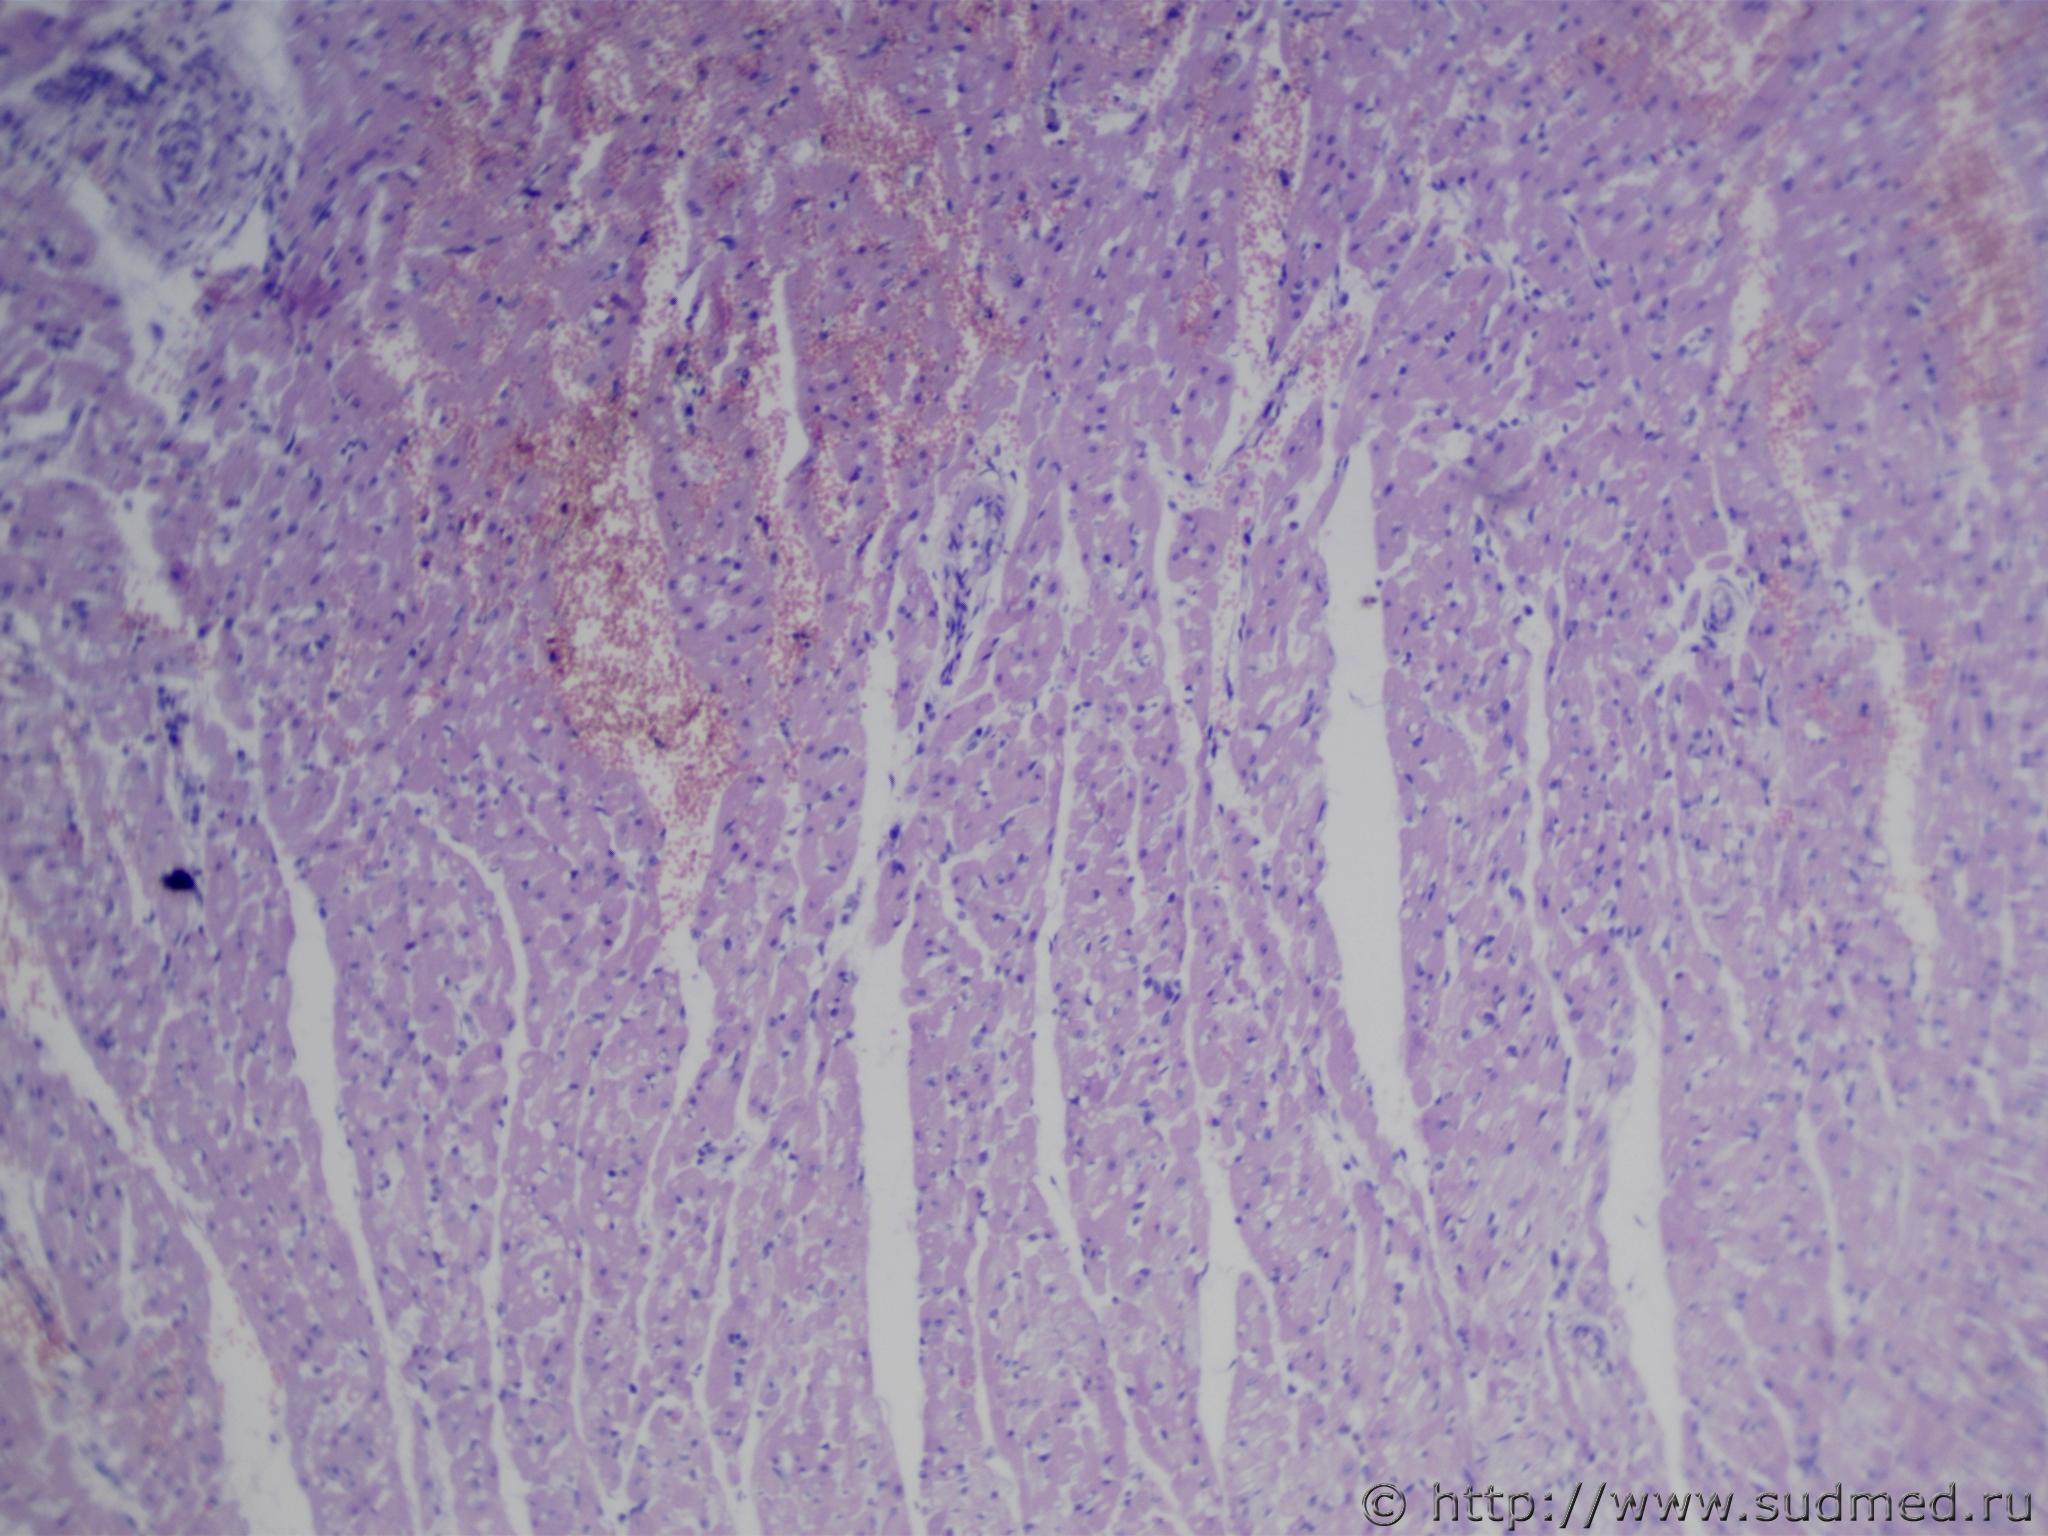

Кошка 8 месяцев. На вскрытии обнаружены полосчатые кровоизлияния миокарда; в области верхушки сердца крупный белый очаг примерно 0,6х0,6см, на мой взгляд, представляющий собой инфаркт. Вопрос в том, что существует мнение, что инфаркт миокарда у кошек и собак невозможен по неясным лично мне причинам. Можно ли говорить об инфаркте в данном случае?

гистология: окраска гематоксилин и эозин (1-4) и ГОФП методом (5-7).

На тех микрофото,что открылись полностью или частично, картина продуктивного миокардита.

каким образом вы вызвали предполагаемого вами инфаркта миокарда т.е. перевязывали ли коронарный сосуд или вызвали эмболизацию либо тромбом? на рисунках имеет место, кроме установленного диагнозом ув.Медиком и добавлю еще ушиб миокарда ввиде стромального кровоизлияния и кардиомиоцитолизиса т.е.повреждения кардиомиоцитов и безядерных и дезориентации ядра(смещения ядра от центра).